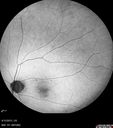

Cat Scratch - Neuroretinitis OD AND retinitis OS - Bartonella henselae positive547 views27 year old female with exposure to cats and prior fever. Reports with recent vision loss right eye. She was treated with doxycycline and within 2 weeks the right eye looks better. Then she skipped all follow-up visits. The right eye presented 20/200 and the left 20/16